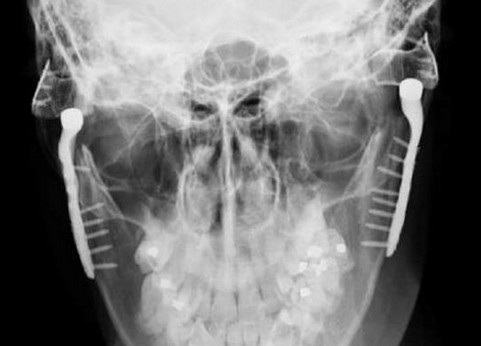

“钛下巴”植入示意图。

来自英国诺丁汉的托妮随后接受了一个罕见的下巴“重置”手术。医生将一副价格高达1.6万英镑(约合15.8万人民币)的钛板材植入到她的下巴里。